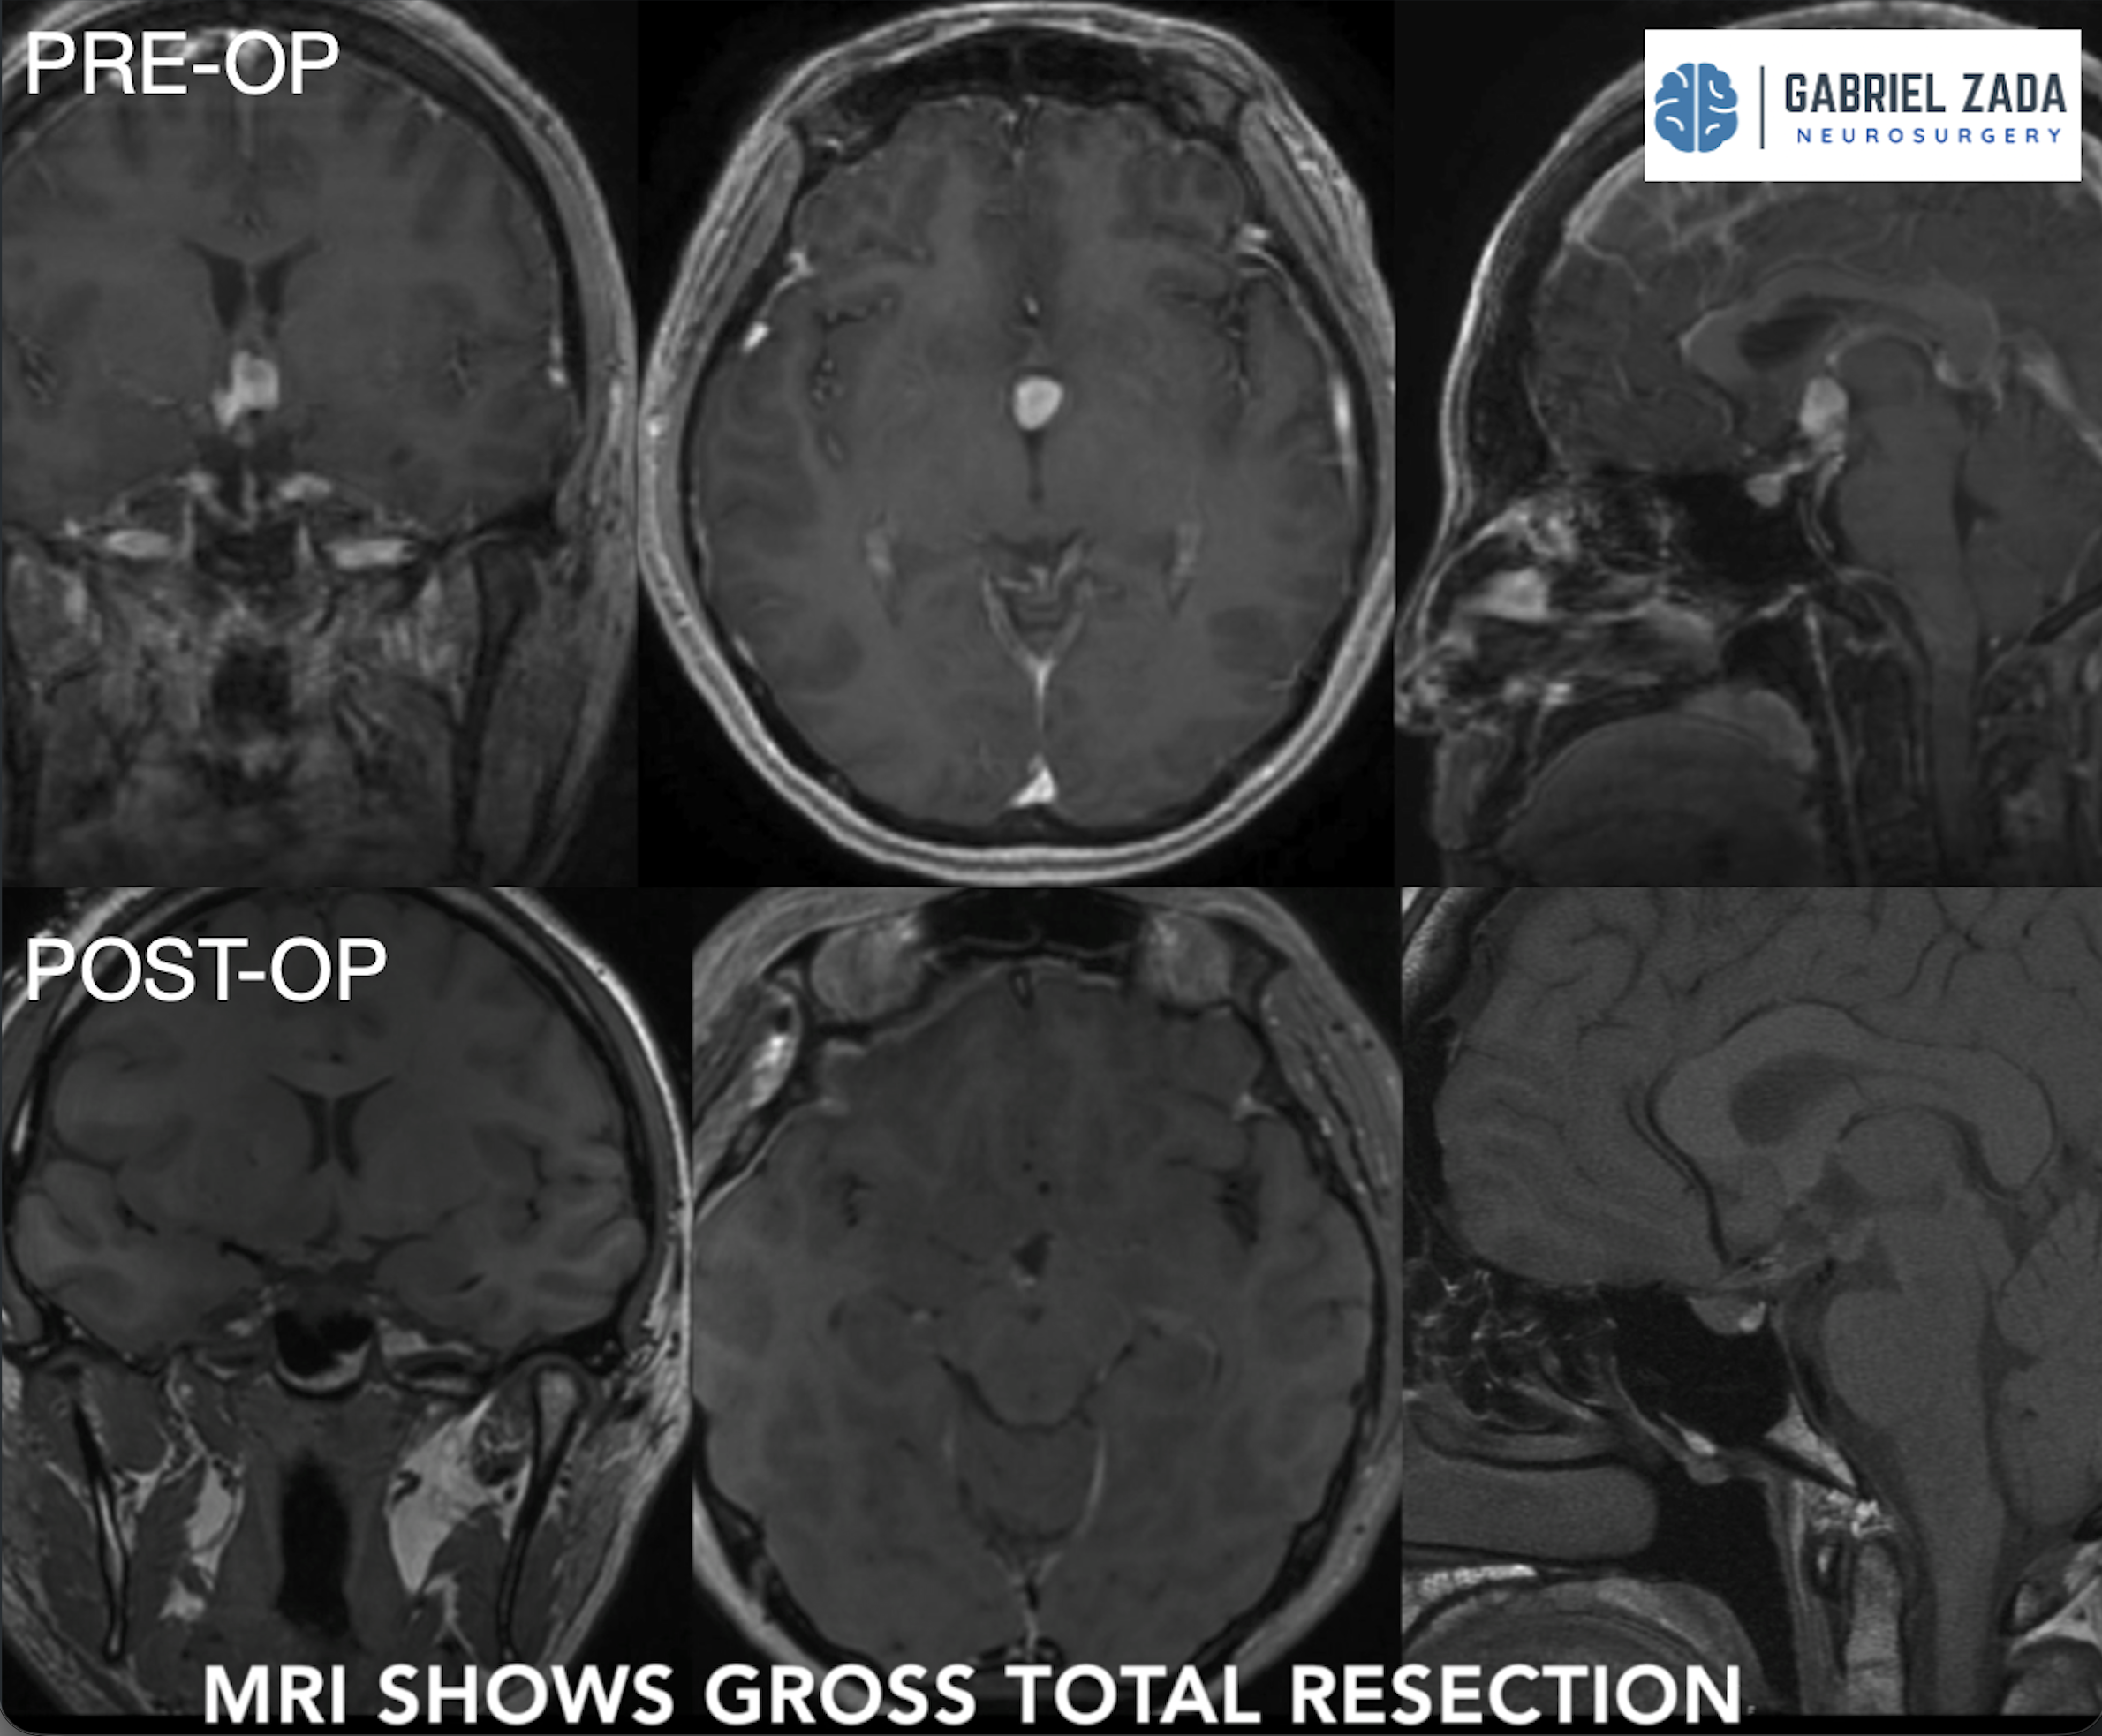

Explore this comprehensive gallery featuring pre‑ and post‑operative imaging of patients with skull‑base tumors treated by Gabriel Zada, MD, MS, FAANS, FACS. These cases highlight Dr. Zada’s expertise in advanced neurosurgical techniques and outcomes.

*Representative cases shown for educational purposes. All images de-identified. Individual results vary.